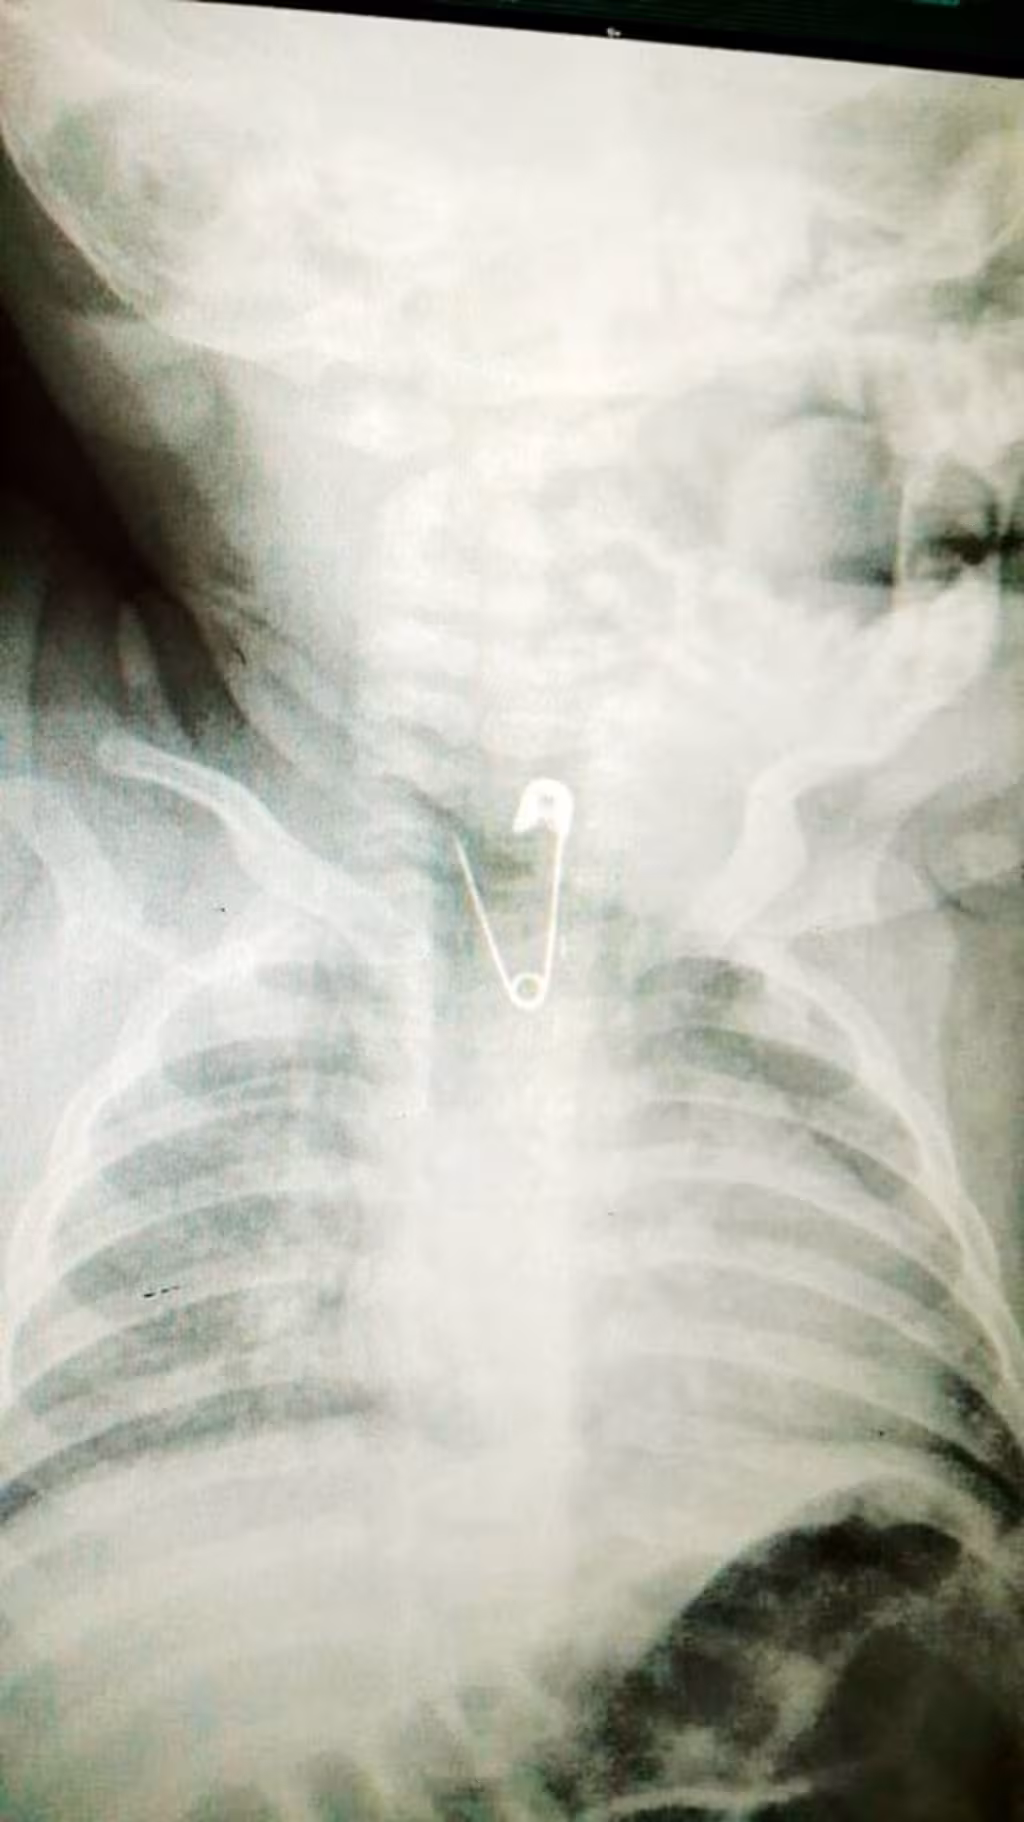

Операція тривала приблизно 30 хвилин, під загальним наркозом, зі штучною вентиляцією легень.

“Ми захопили шпильку за головку й опустили в шлунок. Там більше місця, ніж у тоненькій 8-міліметровій трубці стравоходу, де розвернути двосантиметрову шпильку неможливо. У шлунку ми її повернули й тупим кінцем (гострим донизу) поволі витягли назовні”, — розповів львівський ендоскопіст Віктор Іванців.

Акуратно ввівши ендоскоп і маніпулятор в стравохід, лікарі проштовхнули шпильку в шлунок, там повернули (зробити це вдалося далеко не з першої спроби), і тоді повільно витягували.